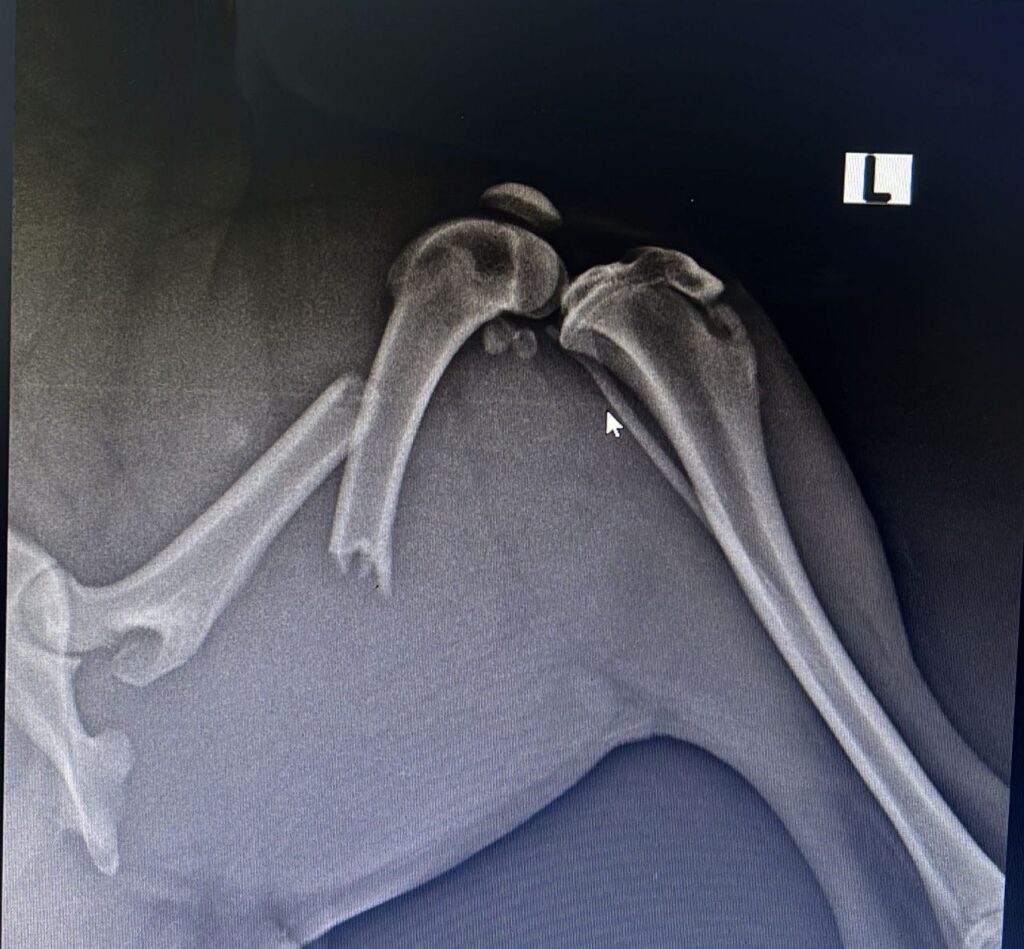

Luego de que la canina fuese revisada por personal médico y se le tomaran varias radiografías; se diagnosticó que ‘Negris’ tiene una fractura en el fémur que requiere de cirugía (de la cual el costo es de aproximadamente $1.800.000, además, de los gastos de consulta y medicamentos que ya le formularon)

Se diagnosticó que ‘Negris’ tiene una fractura en el fémur.